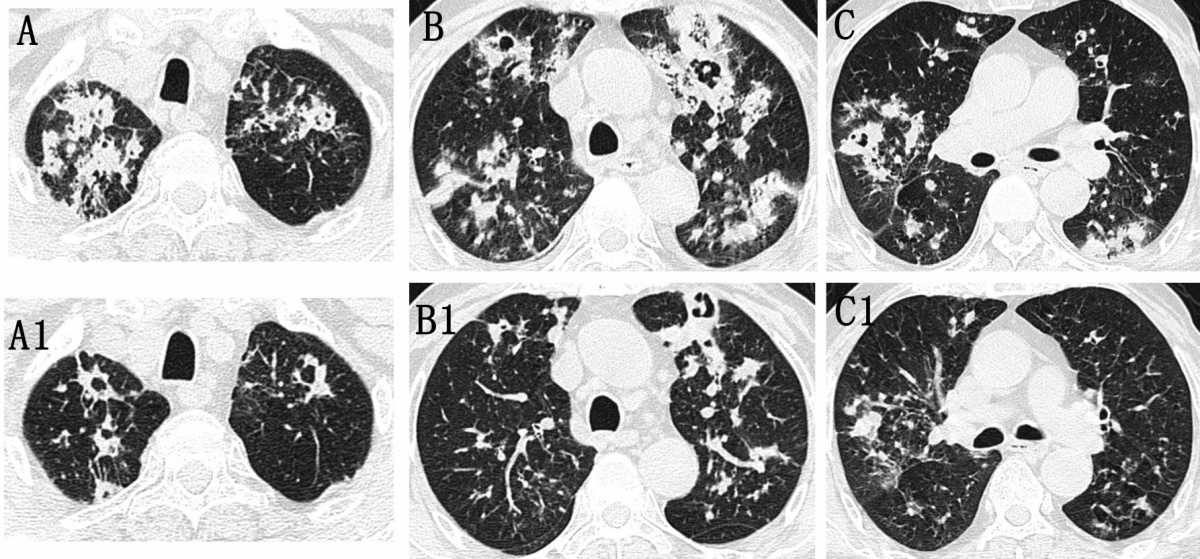

结核型COPD-IPA的胸部CT表现

图像来自一位77岁COPD-IPA患者,因“咳嗽、气短1个月”入院,无肺结核病史。CT扫描显示双上肺多发斑片影及结节状高密度影,部分发展为空洞性病变,与继发性肺结核表现类似。